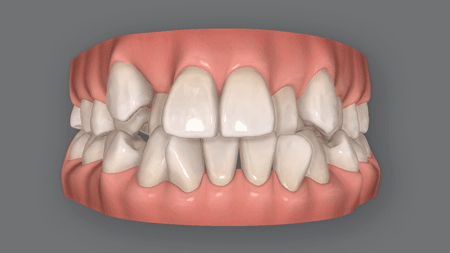

上顎前突(じょうがくぜんとつ)とも呼ばれる出っ歯は、上の前歯が前方に飛び出して見える症状。

出っ歯(上顎前突)の矯正治療により、目立っていた上の前歯が下がり、横顔が整います。前歯が引っ込むだけで、同じ顔なのにずいぶんと印象が違うと思いませんか?

当院のマウスピース矯正(インビザライン)で、こうした変化を実現できます。

※上記はイメージ画像です

※効果には個人差があります

また、上だけでなく下の前歯も飛び出した口ゴボや、歯がガタガタの叢生乱杭歯)、八重歯を併発している患者さまも少なくありませんが、こうした症状も出っ歯の矯正で治せます。